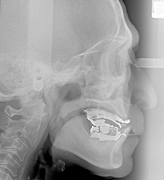

←側面レントゲンにて治療前評価.

(噛み合わせが低く口元が凹んでいます)

↓義歯の設計にあたっては,セファログラム(規格化)

レントゲン分析も併用して問題点を診査します.

軟組織分析(口元突出・口角・E-ライン・オトガイの筋緊張・気道の大きさ),骨分析(下顎関節の位置・頚椎の

湾曲度・下顎の回転度,咬合平面角,かみ合せの高さ)